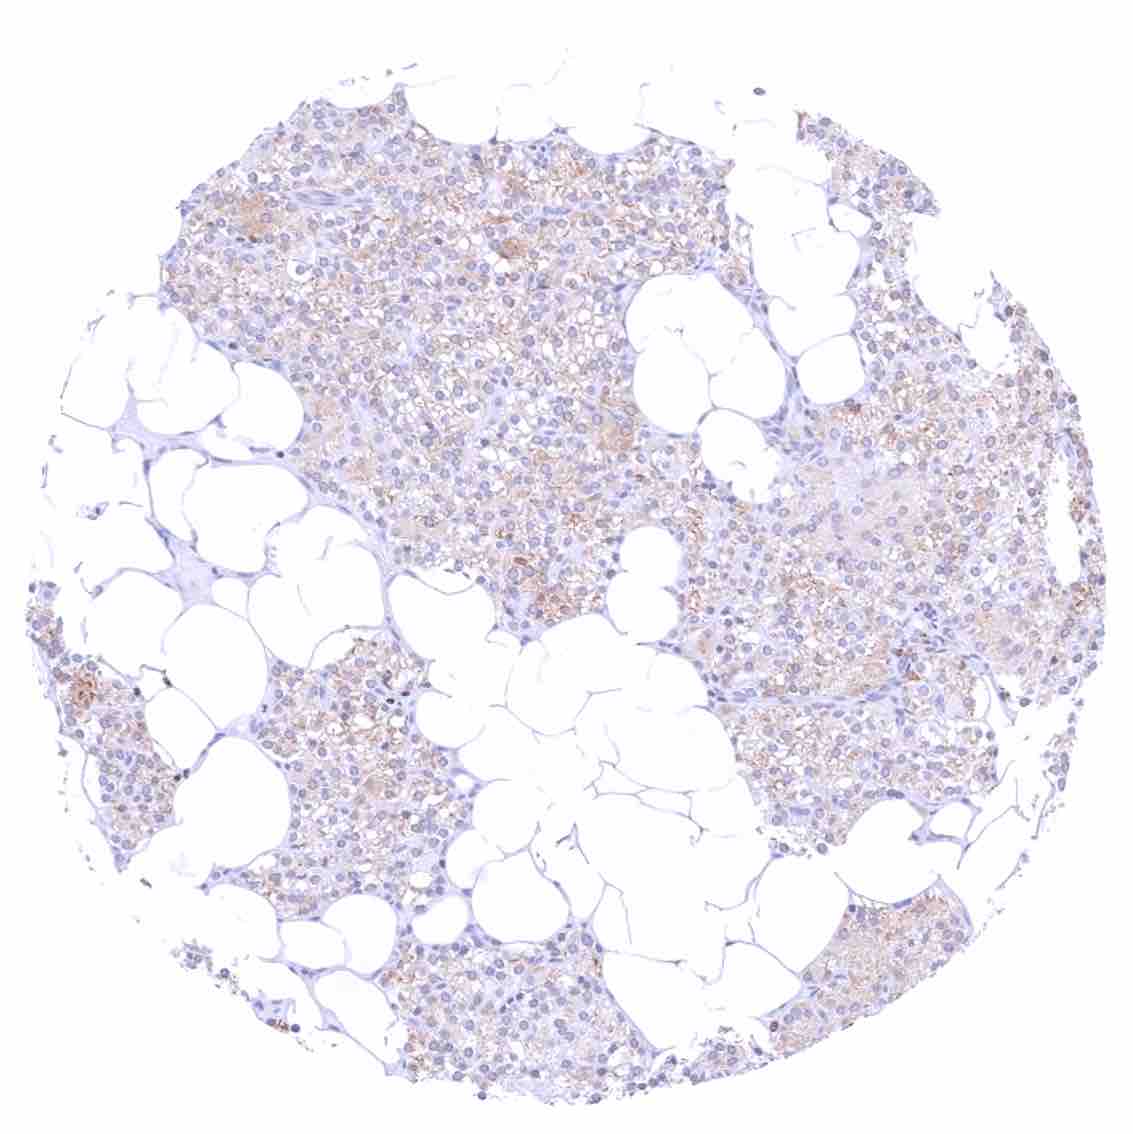

Bone marrow – Only few cells are bcl-2 positive.